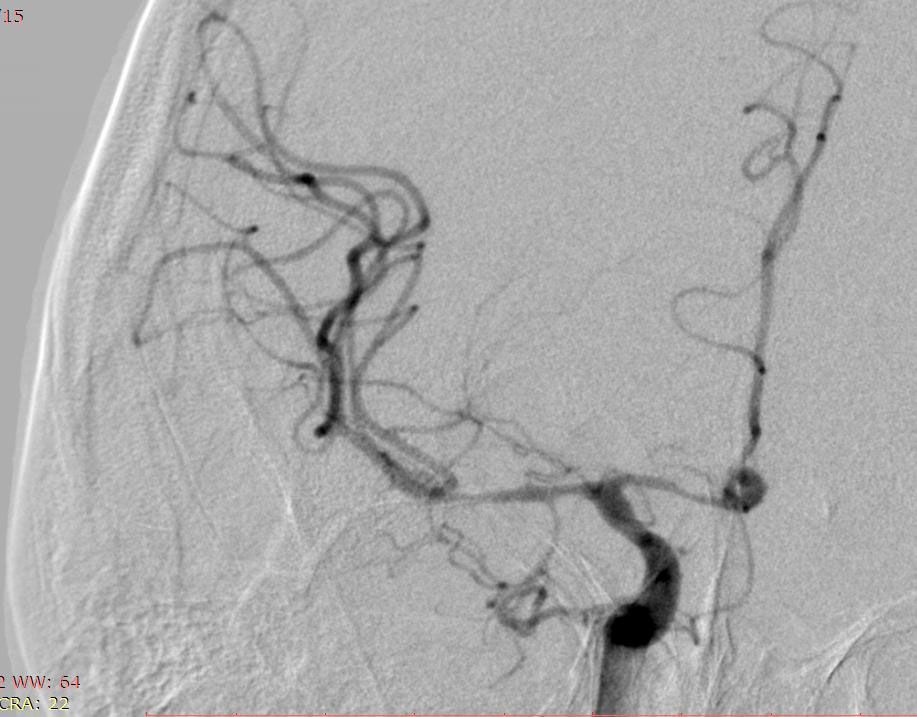

3.05.23 у КНП «ТОКПНЛ» ТОР вперше власними силами була емболізована аневризма судин головного мозку. В результаті розриву аневризми хворий К, 45 років отримав крововилив у мозок. Єдиний шлях лікування такої патології – це виключення аневризми (мішечку у стінці мозкової судини). Ендоваскулярний спосіб до зволяє зробити це без розрізів, безпечно, швидко та надійно. Через прокол на стегні пацієнту було заведено катетер у стегнову артерію та виконано ангіографію – знімок судин головного мозку, де була виявлена аневризма, а також важке ускладнення субарахноідального крововиливу: вазоспазм – звуження просвіту судин головного мозку іноді до повного зупинення кровотоку.

Операція була проведена за допомогою ендоваскулярної емболізації — це мінімально інвазивний метод, який не вимагає відкритого хірургічного втручання на мозку. Через артерію, зазвичай у стегні, лікар вводить тонкий катетер, який проводить безпосередньо до аневризми.

Під час цієї процедури у порожнину аневризми було введено спеціальні спіралі з пам'яттю форми (койли). Ці мікроспіралі скрутилися, утворивши щільний клубочок, що заповнив аневризму та запобіг повторній кровотечі. Додатково була виконана фармангіопластика — введення препаратів для зняття спазму судин, що дозволило безпечно дістатися до ураженої ділянки.

Ця складна операція стала можливою завдяки сучасному ангіографу Siemens Artis One, який надає хірургам чітке зображення судин у реальному часі. Але найголовніший фактор успіху — це злагоджена робота усієї операційної бригади: досвідчених нейрохірургів, анестезіологів, навчених медичних сестер та інших фахівців.